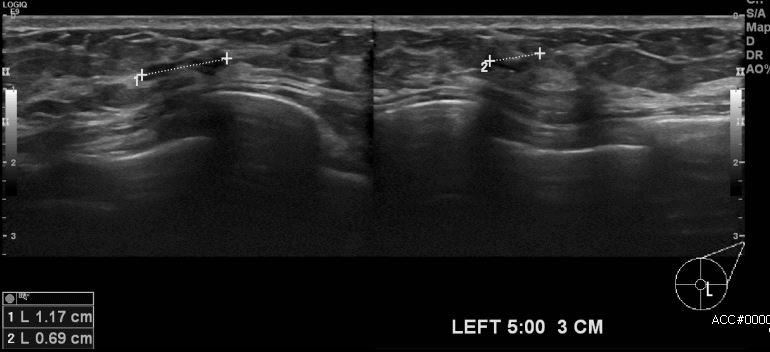

건강검진상 이상소견으로 내원하신 50대 여성분으로 본원 초음파 시행 후 좌측 5시

방향에서 3cm 떨어진 거리의 혹 조직검사 시행하여 좌측 유방의 미세석회포함된 상피내암으로 진단 되었습니다.